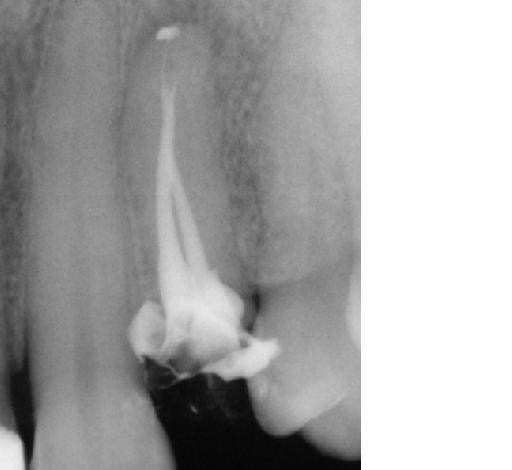

celle la faudra me dire comment on passe sans laser (et comment on y injecte autre chose que de la pate).

sinon: micjhel costeseque obture cortisomol lentulo+laser et ensuite maitre cone gutta (je l'ai vu y'a 15 jours).

le risque pate seule est qu'elle est trés trés compacte et dure.... pas gai pour une reprise de traitement et donc pate seule pour les 2 derniers mm mais cone foulé à chaud ensuite (je sais je faisais pas comme ça "avant" mais j'ai écouté les copains d'eugenol et me suis remis à la gutta.... par contre la digue....).

suite et fin

photo lime en place: pas possible aller + loin même en manuel avec une n°8....

1ere endo: lentulo pate trés fluide

2eme: premier tir et relentulo (pate trés fluide poussée par le laser et + épaisse pour la deuxiéme couche au lentulo)

3eme: deuxieme tir (je voulais chopper les 2 racines....) et relentulo et gutta.

ps: cette dent était donnée pour perdue et la seule proposition faite à la patiente était implant.... (idem pour la 22 qui est certes à refaire/reprendre mais sans doute pas perdue....)

y m'a fallu 30 minutes pour desobturer et réobturer, Sc33 sur tenoçns titane et coiffe provisoire posées cet aprtés midi, endo faite y'a 2 jours et RAS.